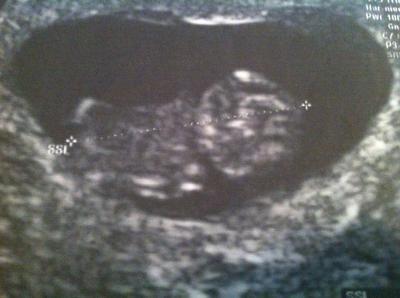

Danke Mädls fürs Daumen drücken hat geholfen! Baby gehts bestens hat uns auch was vor getanzt :-) hat sich die ganze Zeit bewegt es war ein Wahnsinns Gefühl :-) Herz war auch kräftig und gewachsen ist es auch so wie es sein sollte heute 9+1. Bin überglücklich hatte schon Angst weil ich soviel Kreuzweh hab.... Aber es dehnt sich wohl alles und mein vergrößerter Eierstock rechts noch 7 cm drückt anscheinend genau auf einen Nerv. Naja egal nächster Termin wär erst in der 18 Woche.... OH GOTT aber darf eh vorher nochmal kommen so in 4 Wochen ;-) mach ich eine Zwischenuntersuchung egal was es kostet... ;-) so mädls jetzt leg ich die Angst ab unf genieße danke!!!!

Toll so schöne Nachrichten zu hören. Ich muss auch erst wieder am 05.11. zum FA (= 18. SSW). Dachte mir warum so lange, mein FA hat mir aber noch eine Überweisung ins KH gegeben für die Feindiagnostik in der 12.-13.SSW. Werd mir nächste Woche mal einen Termin geben lassen. Wünsch dir einen schönen Abend und eins noch TOLLES SÜSSES Bild

Glückwunsch! Das sieht super aus und so ein süßes Bildchen! Ich gehe auch alle vier Wochen, eigentlich ist wohl nur 3x schallen "im Preis mit inbegriffen", wollen wir uns aber auch nicht nehmen lassen und im zweifelsfall zahl ich die zusätzlichen Schallungen selbst. LG